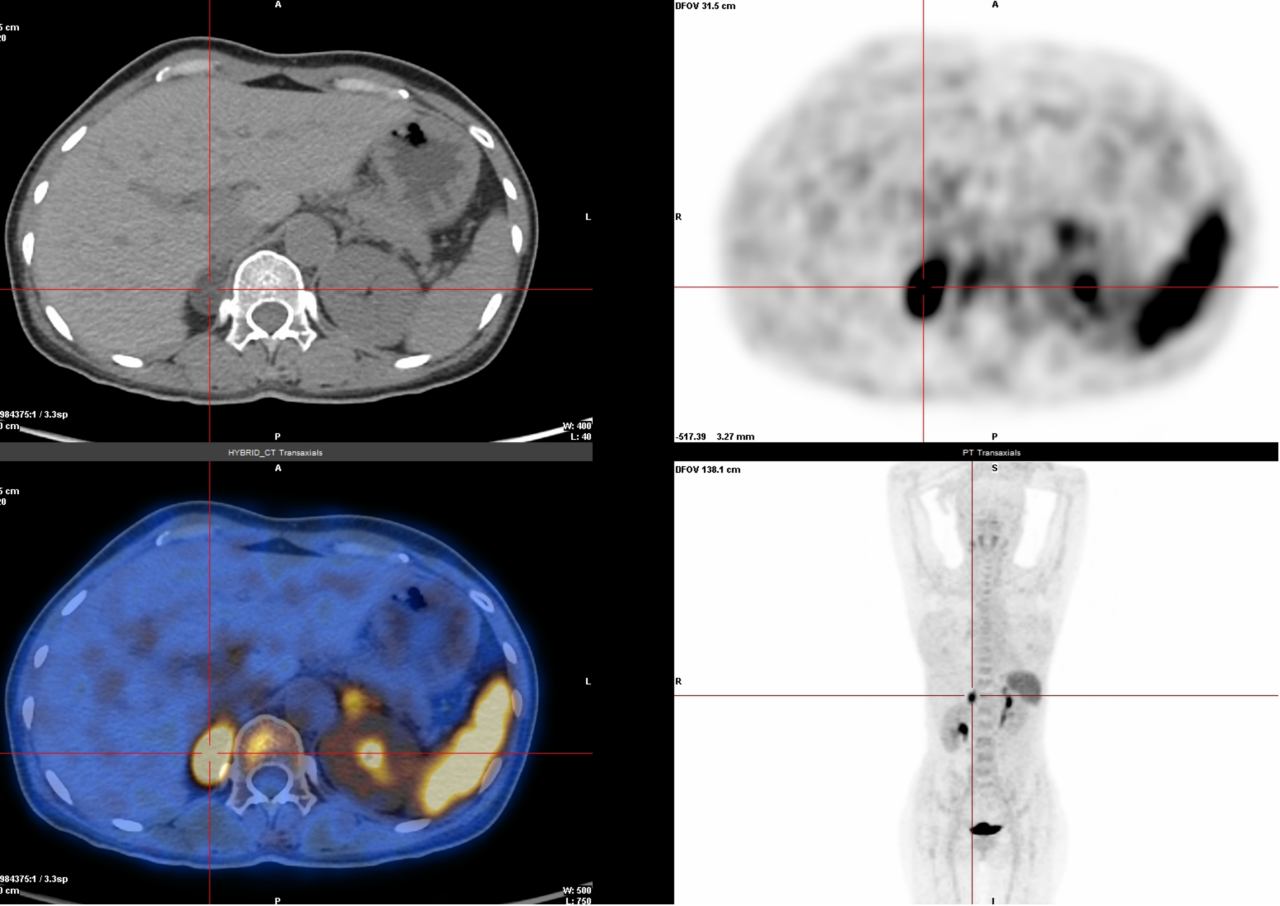

△神经内分泌癌骨骼多发转移

4. 醛固酮瘤、多发性骨髓瘤、惰性淋巴瘤检查(68Ga-Pentixafor):这些肿瘤表面有一种叫CXCR4的“标记物”,这种检查能精准锁定它。